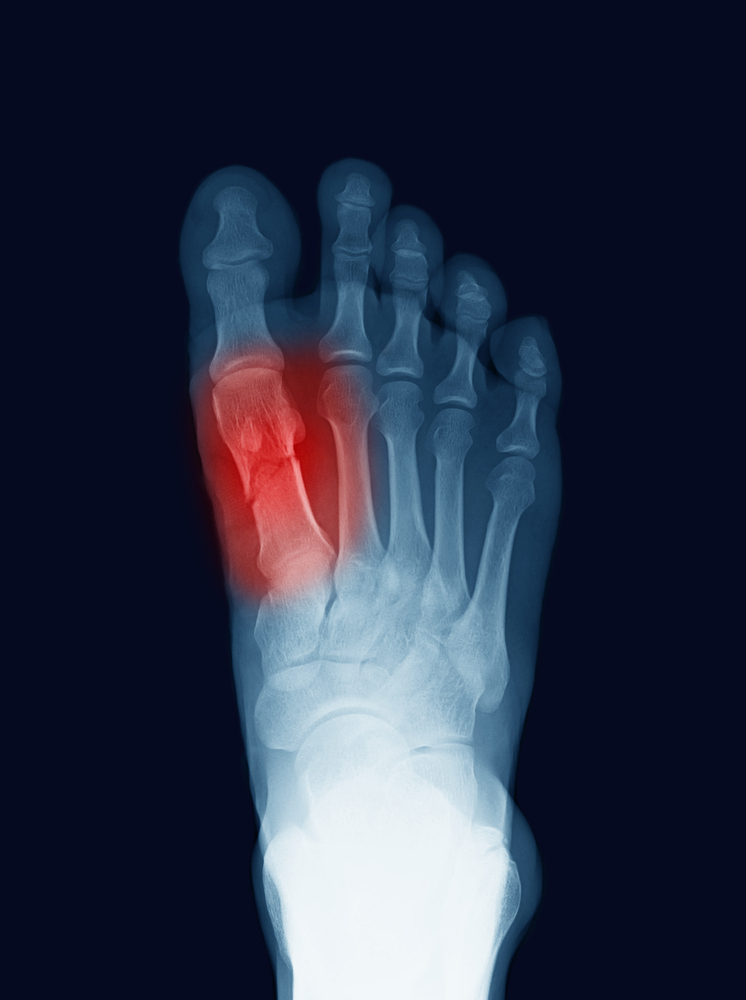

De nombreux patients se demandent s'ils peuvent continuer à marcher avec une fracture du pied, et si oui, quels sont les conseils et précautions à prendre Peut-on marcher avec une fracture du pied ? La réponse à cette question dépend de plusieurs facteurs, notamment de la gravité de la fracture et du traitement qui a été prescrit par le médecin

La reprise des activités dans cette région sera toutefois conseillée une fois que les os se seront suffisamment ressoudés, généralement au bout de quelques. Dans cet article, nous aborderons ces questions et fournirons des recommandations pour. Peut-on marcher avec une fracture du pied ? La réponse à cette question dépend de plusieurs facteurs, notamment de la gravité de la fracture et du traitement qui a été prescrit par le médecin

Fracture du calcanéum Dr BovierLapierre. Marcher avec une fracture du pied peut être difficile et nécessiter certaines précautions pour éviter d'aggraver la blessure Dans certains cas, il est possible de marcher avec une fracture du pied en utilisant des béquilles ou une attelle pour soulager le poids du corps.

Comment savoir si on a une fracture au pied ? comment la soigner ? Santé Magazine. En général, marcher avec une fracture au pied n'est pas recommandé, car cela peut aggraver la blessure, retarder la guérison et causer des complications Marcher avec une fracture du pied est souvent déconseillé, car cela peut aggraver la blessure et prolonger la période de guérison